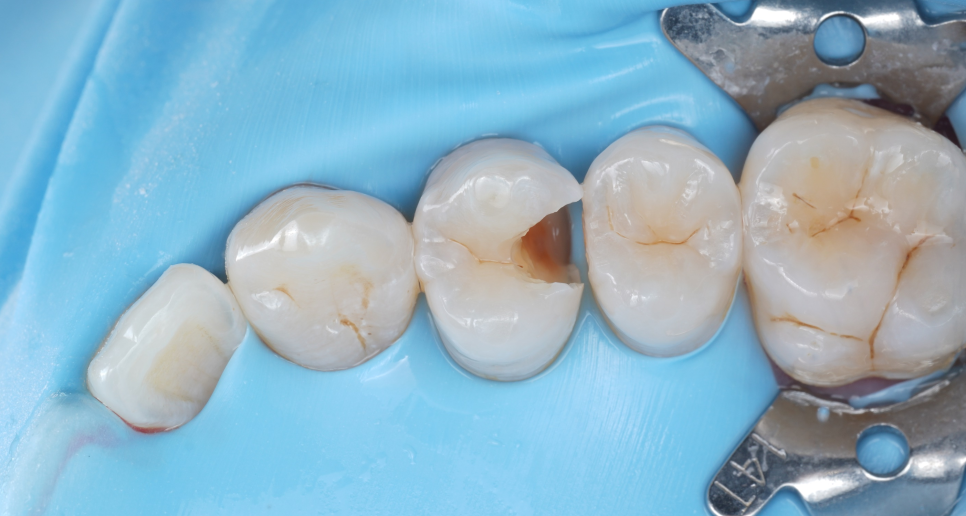

레진의 큰 장점은 ‘최소삭제’예요.

필요한 부분만 아주 조심스럽게 제거하고 치아 본래의 구조를 최대한 보존할 수 있죠.

촬영일 : 251020

반면 인레이나 크라운은 충치가 있든 없든 치아 전체를 덮어야 하니 자연치가 많이 깎일 수밖에 없는데요.

한 번 삭제된 치아는 복원되지 않기 때문에 저는 항상 ‘지킬 수 있다면 지키자’는 마음으로 치료하고 있어요😊

그래서 이번에도 굳이 크라운으로 가지 않고 레진 빌드업으로 다시 살려보기로 결정했죠.

이 재료보다 삭제량이 적은 치료는 없기 때문에 저는 레진을 정말.. 정말 애정한답니다🫰